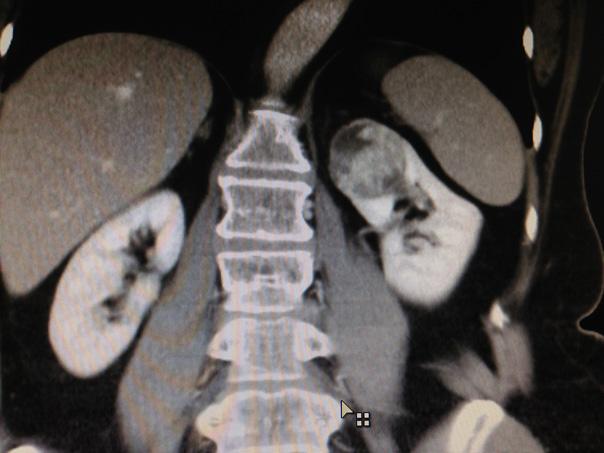

- un scanner de l’abdomen et du thorax est nécessaire pour rechercher si la tumeur s’accompagne d’adénopathies (ganglions), d’une atteinte d’une veine rénale ou de la veine cave, ou de métastases pulmonaire, osseuse ou hépatique.

Fig 1 : Les différentes localisations tumorales